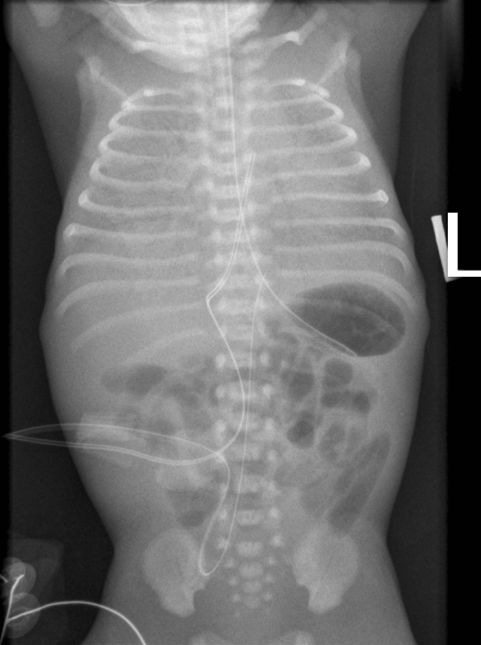

Pneumoni hos nyfødt, røntgen .

• Rtg. thorax kan påvise bilaterale infiltrater og pleuraeksudat hos 2/3 med pneumoni